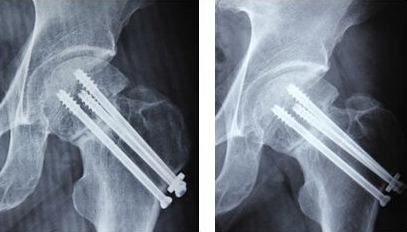

老年人发现股骨头骨折的情况怎么锻炼?

郑州股骨头坏死医院介绍这主要还是根据病人股骨头骨折采用的治疗方法来决定的,如果病人可…[详情]